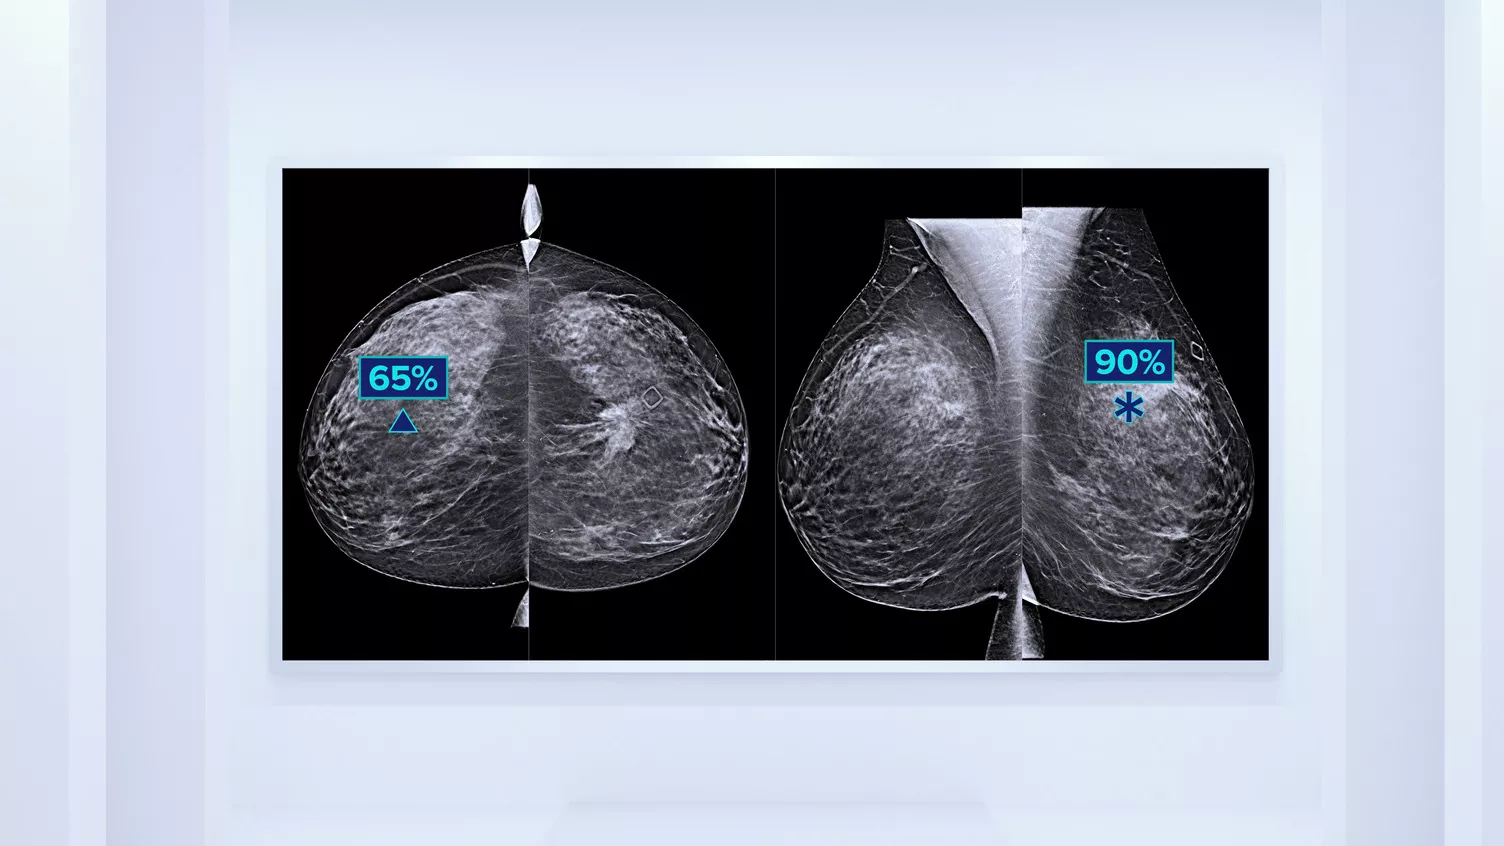

In addition to volume, pattern and texture of fibroglandular tissue may play just as an important role in mammographic cancer risk prediction.3-5 By analysing and categorising breast texture and pattern, our technology can deliver the accurate information you need to achieve more consistent and reliable scoring and confidently design patient-specific screening.

Objective machine learning algorithm that assigns breast density category based on analysis of breast tissue texture and patterns.

Quantra software’s unbiased algorithm analyse both 2D and tomosynthesis images to support your analysis by:

- Overcoming subjectivity in visual assessment, providing more consistent, and more reliable scoring.*

*Scores are based on ACR BI-RADS categories, in line with the revised guidance by the American College of Radiation (ACR) BI-RADS Atlas 5th Edition. This accounts for pattern and texture, compared with volume, when determining density.